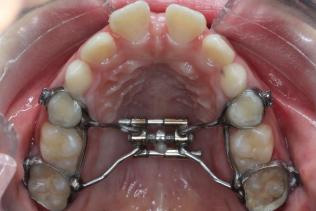

图 1 扩弓器佩戴时